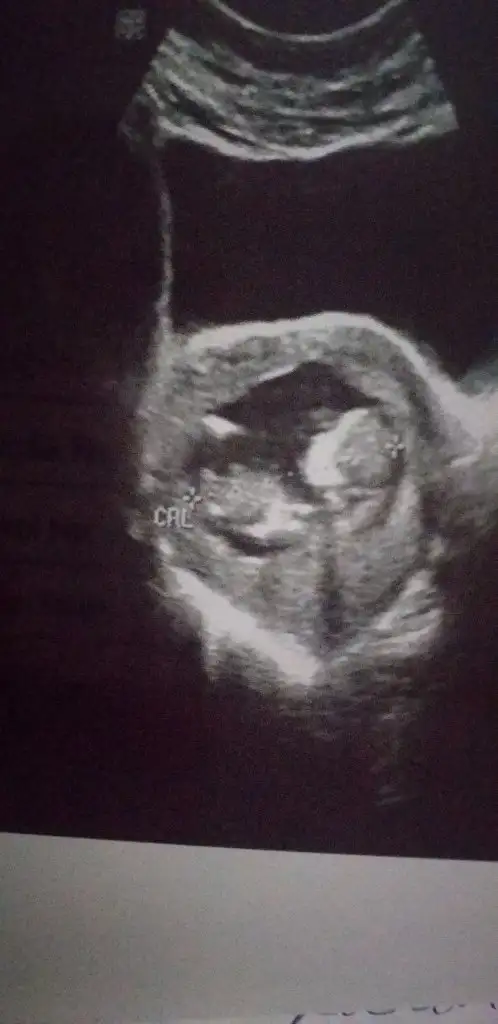

Kiz mi diyosun bnmde icime oyle doguyor hayrlisi olsun insallah canmkız gibi

Sizinki de erkeğe benziyor ama çok iyi göremedim sağlıkla hayırla gönlünüze göre olsun inşAllah

Erkeğe benziyor goruntusuKizlar 12 haftalik bebegimin cinsiyet tahmini yapar misiniz cok merak ediyorum :) Eki Görüntüle 2685687